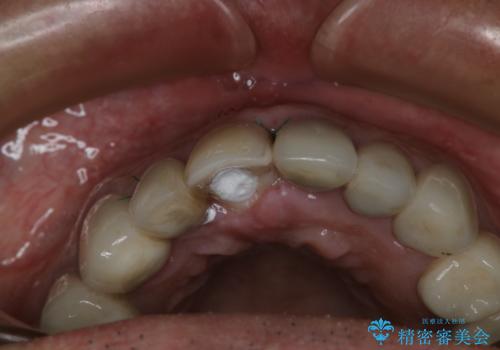

- 事故による外傷で前歯に歯根が真っ二つに折れてしまい、保存不可能となってしまった部分にインプラント治療を計画しました。

患者様のご要望もあり、審美性の確保ができる抜歯早期埋入→埋入後即時荷重という手術法を取りました。

近年、インプラントの素材や手術法の研究が進み、保存不可能となった歯牙に対して抜歯してすぐインプラントを埋入し、さらに直後から仮歯がを入れ噛むことができる【抜歯即時埋入】【即時荷重】という技法が確立されました。

従来、前歯部分のインプラントでは周囲に残っている自身の歯に仮歯を張り付けることで審美性を保ってきましたが、脱離を繰り返したり食事に耐える強度を保つのが難しいという側面がありました。